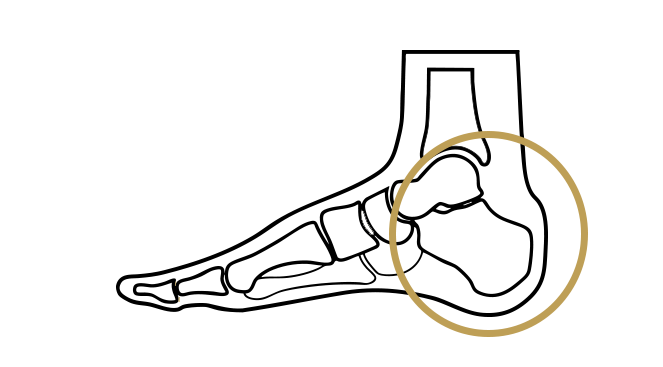

Erkrankungen des Rückfußes

Der Rückfuß bildet die Basis für Stabilität und Bewegung des Fußes und ist besonders belastet bei Gehen und Stehen. In dieser Kategorie erhalten Sie einen Überblick über häufige Erkrankungen des Rückfußes, deren Ursachen, typische Symptome und mögliche Therapiemöglichkeiten.

Bildquelle: www.docset.de

Symptome

Viele Menschen mit einem Hohlfuß haben keine Beschwerden. Bei anderen können jedoch Schmerzen im Fuß, Knöchel oder Bein auftreten, insbesondere nach längerer Belastung. Auch eine Instabilität des Fußes, eine erhöhte Anfälligkeit für Verstauchungen, Druckstellen unter den Mittelfußköpfchen und an der Ferse sowie Hammerzehen können auftreten.

Ursachen

Die Ursachen können vielfältig sein. Neurologische Erkrankungen, Muskeldystrophien, angeborene Fehlbildungen oder auch Verletzungen können eine Rolle spielen. In manchen Fällen ist die Ursache jedoch unklar.

Konservative Therapie

Das Tragen von Schuhen mit guter Dämpfung und Unterstützung, Einlagen zur Druckentlastung und Stabilisierung des Fußes, Physiotherapie zur Verbesserung der Beweglichkeit und Kräftigung der Muskulatur können die Beschwerden lindern.

Operative Therapie

In schweren Fällen, wenn die konservativen Maßnahmen nicht ausreichend helfen und die Beschwerden den Alltag erheblich beeinträchtigen, kann eine Operation in Erwägung gezogen werden. Dabei werden je nach Ursache und Ausprägung des Hohlfußes verschiedene operative Verfahren eingesetzt, um das Fußgewölbe zu korrigieren und die Fehlstellung zu beheben.